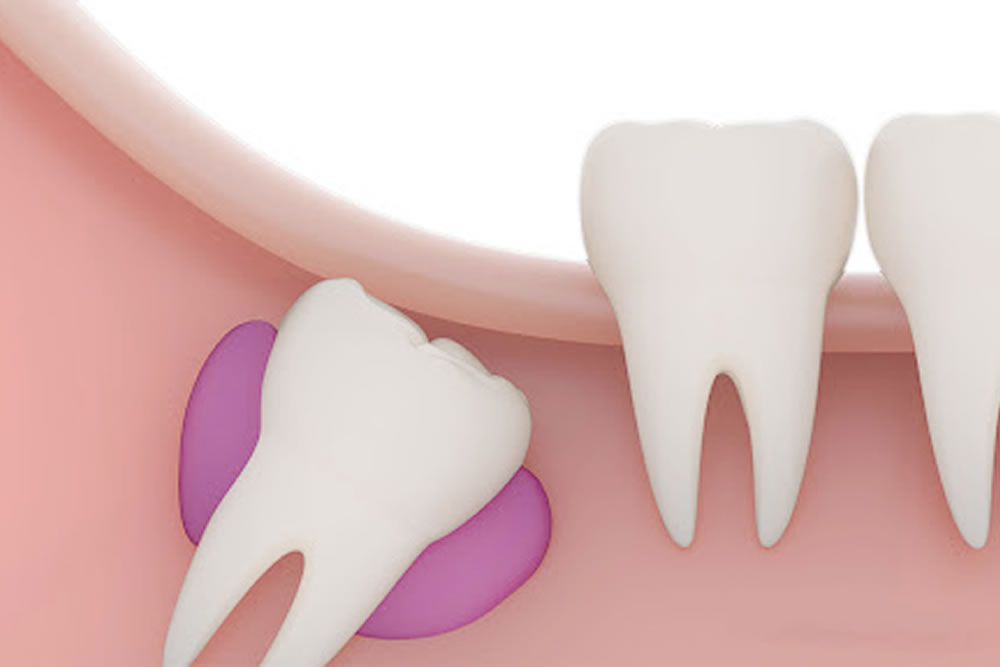

歯並びが悪くなる可能性がある

横向きや斜め向きに生えている親知らずは、成長の過程で前方の歯を押すような状態になります。継続的に押された前方の歯は少しずつ動き、将来的に歯並びや咬み合わせが悪くなる可能性が高くなるため、できるだけ早めの抜歯をおすすめいたします。